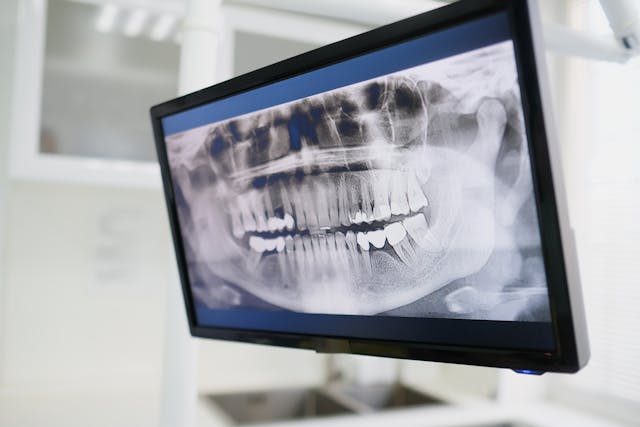

Tomografia zębów to badanie obrazowe, które pozwala dokładnie ocenić struktury jamy ustnej w trzech wymiarach. W przeciwieństwie do standardowych zdjęć RTG umożliwia analizę nie tylko powierzchni zębów, ale również tkanek głębokich i kości. Dzięki temu znajduje zastosowanie w diagnostyce przypadków wymagających precyzyjnej oceny.

Tomografia zębów Wrocław pozwala wykryć próchnicę w trudno dostępnych miejscach, które nie są widoczne na tradycyjnych zdjęciach. Dotyczy to szczególnie przestrzeni międzyzębowych oraz obszarów pod wypełnieniami.

Badanie umożliwia także ocenę głębokości zmian i stopnia zniszczenia tkanek zęba. Ma to znaczenie przy planowaniu leczenia.

Tomografia dokładnie pokazuje struktury wokół korzeni zębów. Dzięki temu możliwe jest wykrycie stanów zapalnych, torbieli oraz innych zmian w kości.

Pozwala to ocenić rozległość problemu oraz dobrać odpowiednią metodę leczenia, zwłaszcza w przypadku leczenia kanałowego.

Budowa i przebieg kanałów korzeniowych

Badanie umożliwia dokładną analizę anatomii kanałów korzeniowych. Ma to znaczenie w leczeniu endodontycznym, gdzie precyzja jest kluczowa.